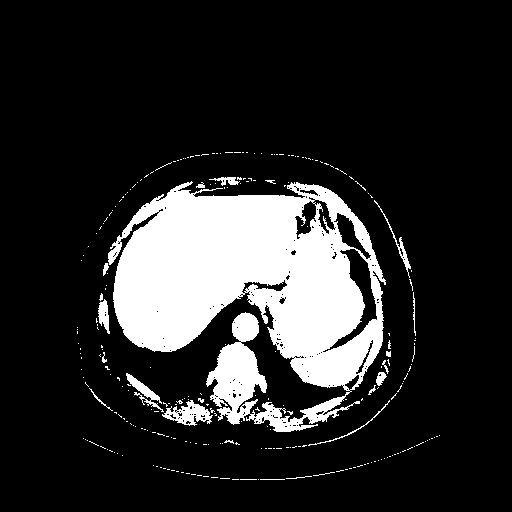

Original VENOUS CT scan

Full window (WL 1023.5, WW 4095 β†’ Low βˆ’1024, High +3071)

Actual HU range: [-1024.0, 3071.0]